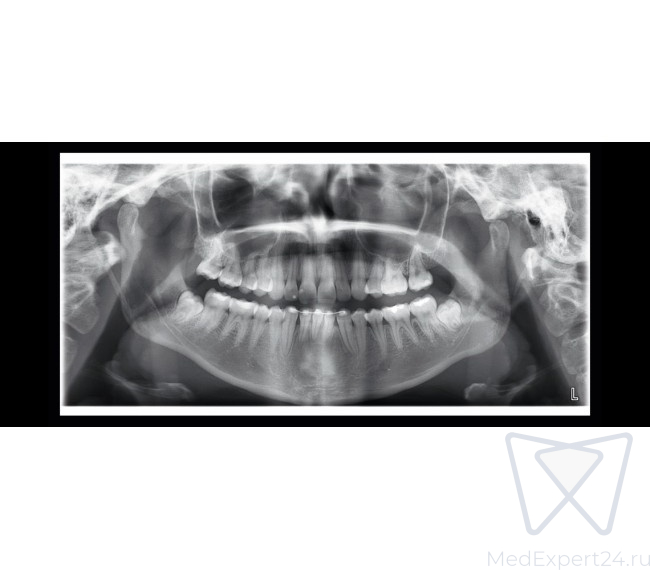

Planmeca ProOne - это полнофункциональный панорамный рентгеновский аппарат, работающий полностью в цифровом формате. Благодаря передовым инновациям, он сочетает в себе большие диагностические возможности и превосходное качество изображения в компактном и простом в использовании аппарате. Широкий выбор программ облучения и параметров графического интерфейса для пользователя гарантируют, что рентгенологические исследования всех видов выполняются очень быстро и без каких-либо усилий. Будучи небольшого размера, установка Planmeca ProOne предоставляет все преимущества цифрового изображения.

6 стандартных программ:

- Стандартная панорама взрослого,

- Стандартная панорама детская,

- Боковая и двойная ВНЧС программа,

- Задне-передняя двойная ВНЧС программа,

- Программа PA-вращающегося синуса,

- Горизонтальное и вертикальное сегментирование